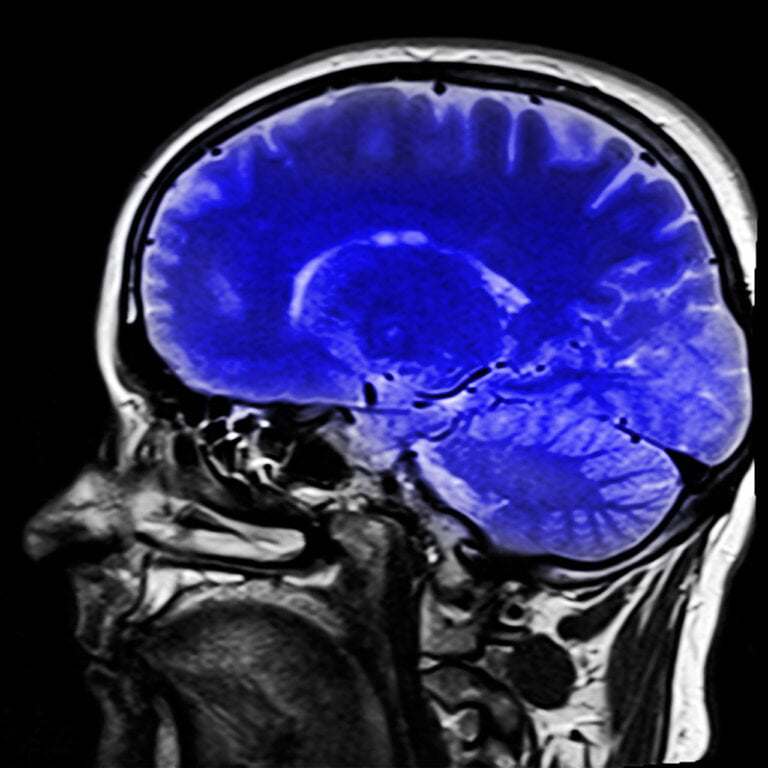

Lyme Disease and Its Effects on the Brain Lyme disease is a bacterial infection caused by the Borrelia bacterium.